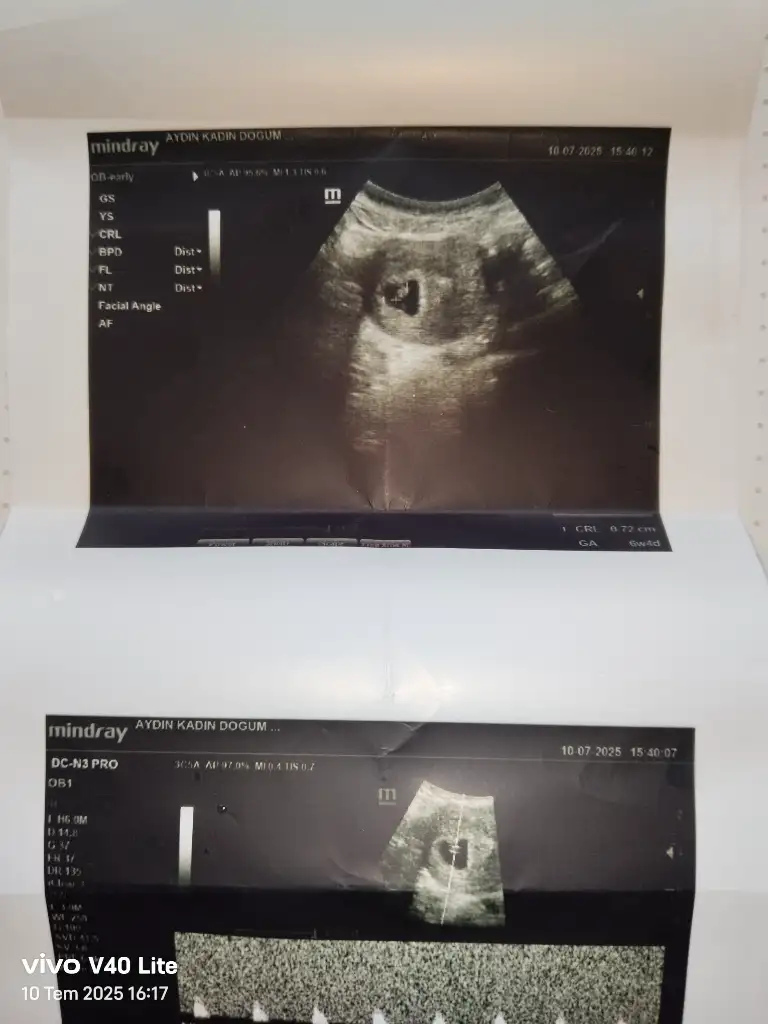

Yorum yaparmısınız. Biri 11hafta 6günlük. Diger 16 haftaKızzzz

kızYorum yaparmısınız. Biri 11hafta 6günlük. Diger 16 hafta

Erkek gibi geldi banaYorum yaparmısınız. Biri 11hafta 6günlük. Diger 16 hafta

Sizinde erkek

Erkek :) givi duruyor ama Allah gönlünüzdekini versinYorum yaparmısınız. Biri 11hafta 6günlük. Diger 16 hafta